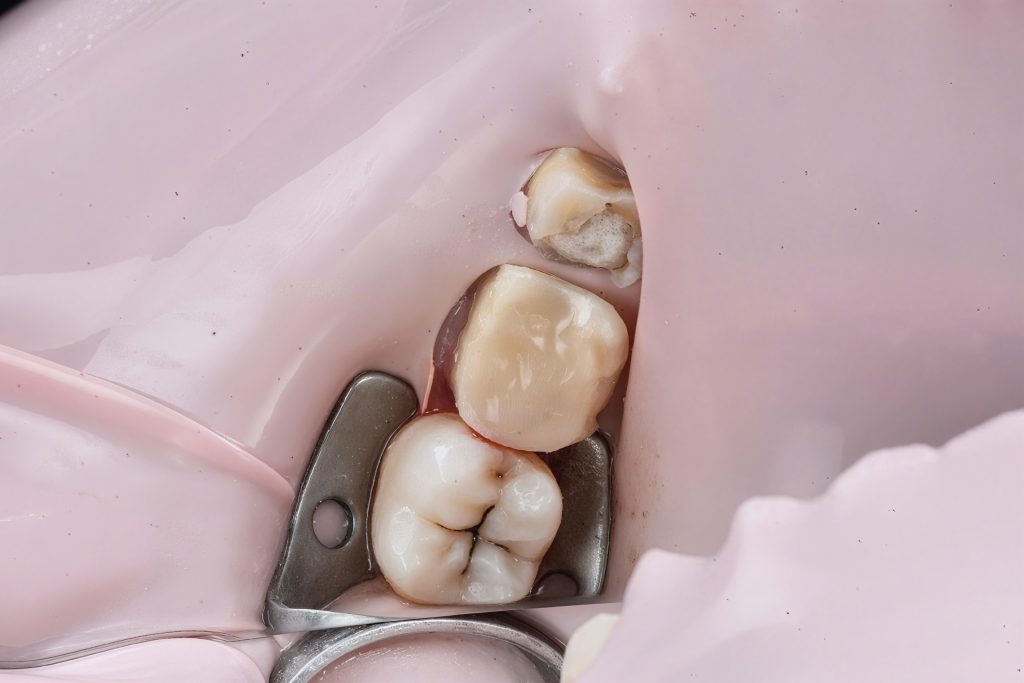

Cervical margin elevated using GC EverX Flow with the matrix-within-matrix technique to re-establish a supragingival margin (Fig 6). Short fibers within the flowable composite acted as an internal stress-absorbing scaffold.

- Fig 6: DME performed with GC EverX Flow.